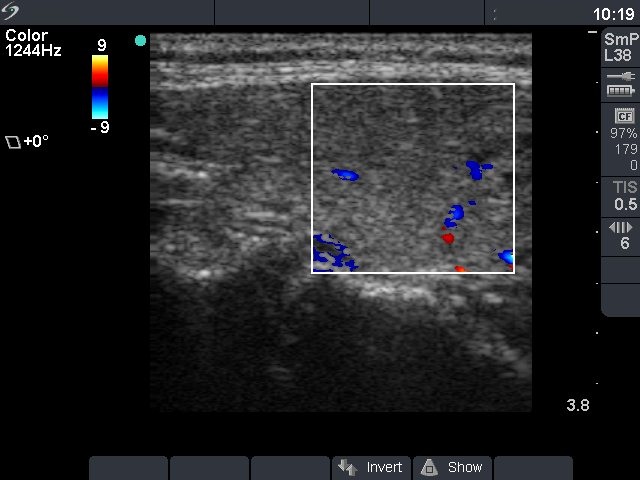

Ultrasonography: the thyroid was diffusely hypoechogenic without any nodule. The vascularization was increased.Thyrostatic drug was administered and the patient went on regular follow-up examinations.

Ultrasonography: compared with the former examination both the size, the echogenicity and the vascularization had normalized except for small hypoechogenic areas with less than 10% of echogenicity index. However, a hypoechogenic nodule with microcalcifications and irregular borders appeared in the left lobe.Cytological picture: there isn't any colloid on the smear. Thyrocytes in irregular clusters with nuclear crowding and overlapping. Thyrocytes are enlarged. Many follicular cells exhibit groove and inclusion. Cytological diagnosis: papillary cancer.